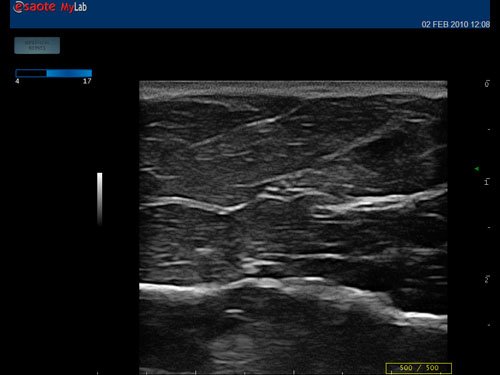

Das MyLab™One steht für das revolutionäre „Arm-held“ Hochleistungs-Ultraschallsystem mit 12”-Full-Touchscreen. Aufgrund seines geringen Gewichts und der Tragbarkeit kann es auch ohne Arbeitsfläche verwendet werden. Eine einzelne Person kann dieses Gerät aufgrund seiner einzigartigen Funktionen allein und selbstständig bedienen.

Das Ultraschallsystem MyLab™One zeigt exemplarisch den modernen Bedarf an Diagnosekapazitäten in verschiedenen Anwendungsbereichen: Radiologie, Kardiologie, Phlebologie, Frauenheilkunde, Orthopädie, Regionalanästhesie, Sportmedizin, Interventionell, Rheumatologie, Erste Hilfe, Notfallmedizin, Vaskuläre Reihenuntersuchungen, Allgemeinpraxis.

Der intuitive Touchscreen bietet dem Benutzer schnellen und einfachen Zugang zu allen Steuerungsfunktionen. Mit der beeindruckenden Bildqualität und einem kompakten Design wird MyLab™One zur idealen Ultraschalllösung am Point-of-Care.